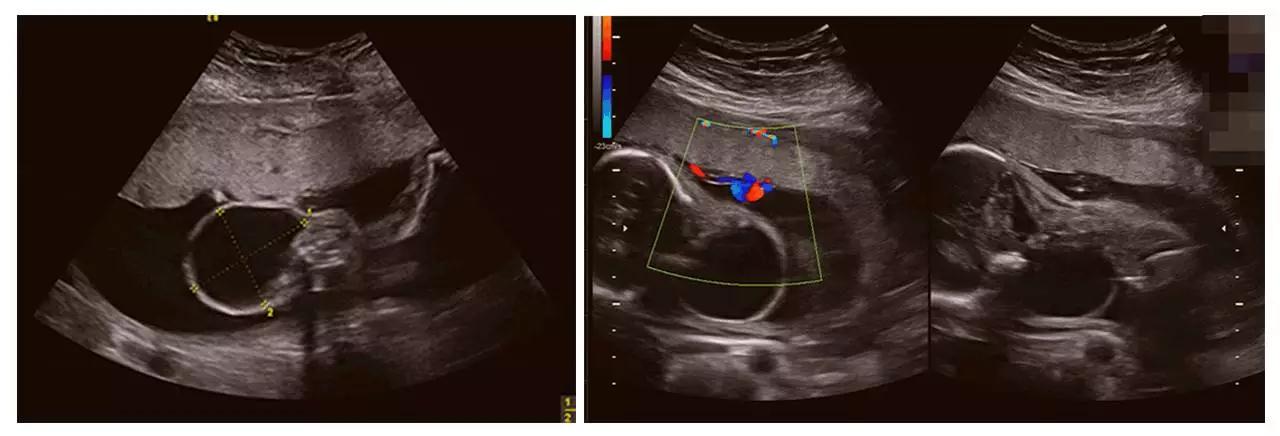

成功筛查胎儿畸形的案例(部分)

(右手多指畸形)

(左心发育不良)

以上案例更多的是警示我们四维彩超(四维彩超)检查的重要性。我们希望每个宝宝都能健康成长。